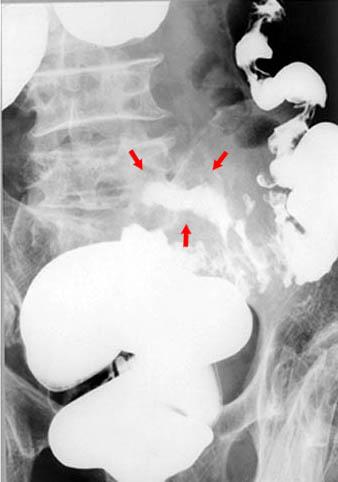

A operated case of diverticular abscess of the sigmoid colon.

Diverticulum/Diverticulitis, Peridiverticular Abscess

Location

Large intestine(Colon)/Sigmoid colon

Technique, Method